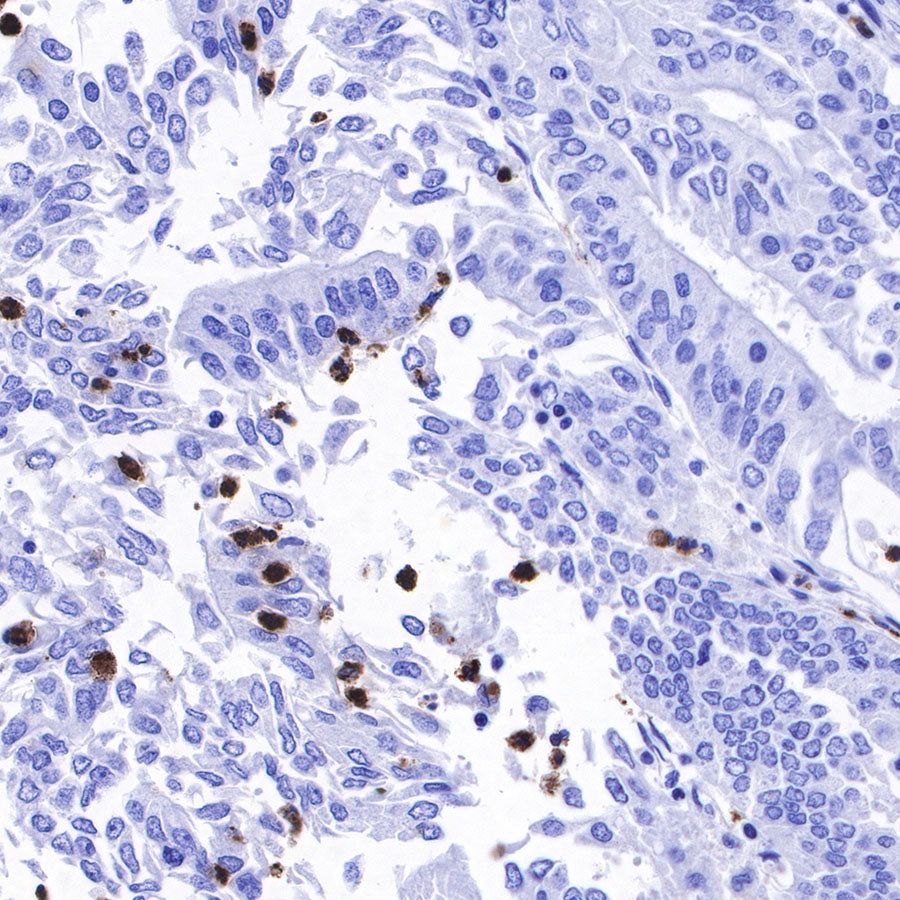

IHC shows positive staining in paraffin-embedded human liver. Anti-Lysozyme antibody was used at 1/100 dilution, followed by a HRP Polymer for Mouse & Rabbit IgG (ready to use). Counterstained with hematoxylin. Heat mediated antigen retrieval with Tris/EDTA buffer pH9.0 was performed before commencing with IHC staining protocol.

IHC shows positive staining in paraffin-embedded human tonsil. Anti-Lysozyme antibody was used at 1/100 dilution, followed by a HRP Polymer for Mouse & Rabbit IgG (ready to use). Counterstained with hematoxylin. Heat mediated antigen retrieval with Tris/EDTA buffer pH9.0 was performed before commencing with IHC staining protocol.

IHC shows positive staining in paraffin-embedded human spleen. Anti-Lysozyme antibody was used at 1/100 dilution, followed by a HRP Polymer for Mouse & Rabbit IgG (ready to use). Counterstained with hematoxylin. Heat mediated antigen retrieval with Tris/EDTA buffer pH9.0 was performed before commencing with IHC staining protocol.

IHC shows positive staining in paraffin-embedded human colon cancer. Anti-Lysozyme antibody was used at 1/100 dilution, followed by a HRP Polymer for Mouse & Rabbit IgG (ready to use). Counterstained with hematoxylin. Heat mediated antigen retrieval with Tris/EDTA buffer pH9.0 was performed before commencing with IHC staining protocol.

IHC shows positive staining in paraffin-embedded human ovarian cancer. Anti-Lysozyme antibody was used at 1/100 dilution, followed by a HRP Polymer for Mouse & Rabbit IgG (ready to use). Counterstained with hematoxylin. Heat mediated antigen retrieval with Tris/EDTA buffer pH9.0 was performed before commencing with IHC staining protocol.

IHC shows positive staining in paraffin-embedded human lung squamous cell carcinoma. Anti-Lysozyme antibody was used at 1/100 dilution, followed by a HRP Polymer for Mouse & Rabbit IgG (ready to use). Counterstained with hematoxylin. Heat mediated antigen retrieval with Tris/EDTA buffer pH9.0 was performed before commencing with IHC staining protocol.

IHC shows positive staining in paraffin-embedded human endometrial carcinoma. Anti-Lysozyme antibody was used at 1/100 dilution, followed by a HRP Polymer for Mouse & Rabbit IgG (ready to use). Counterstained with hematoxylin. Heat mediated antigen retrieval with Tris/EDTA buffer pH9.0 was performed before commencing with IHC staining protocol.